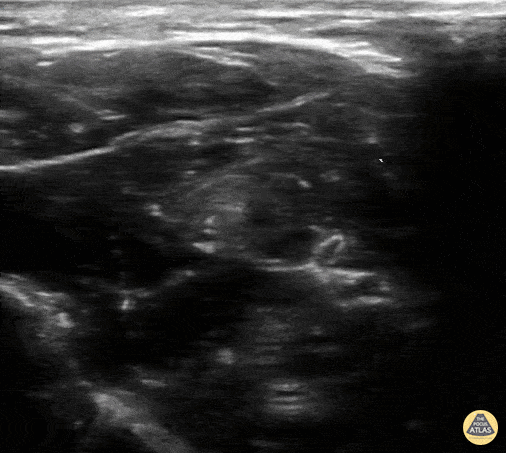

13 yo male with a palmer laceration. Median nerve block performed with good anesthesia. Needle coming from left of screen. Contributor: Paul Khalil, MD Nicklaus Children's Hospital @khalil3paul